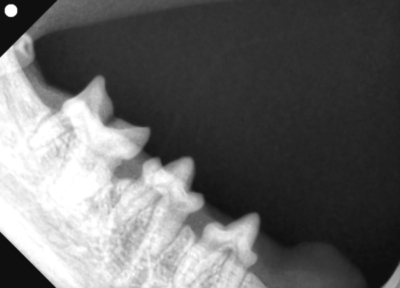

そして歯科レントゲン撮影を行いました。

なにがなにやらわからないと思い、黄色ラインで歯をなぞりました。右上顎です。中央に過剰な歯があり、回転して生えています。

左下顎は正常な数と歯並び

右上顎も同様に中央に回転して生えている過剰歯があります。

左下顎は中央に重なって生えている過剰歯があります。レントゲンで確認しても、乳歯ではなく永久歯と考えられました。これらは過剰歯と呼ばれ、通常より本数が多く歯が生えてきます。かみ合わせが悪くなり、また歯間が狭くなり歯垢がつき、歯周病になりやすいです。そのため、不必要と思われる歯を抜歯しました。また、歯肉の増殖している部分を一部切り取り病理検査用の検体とし、それ以外の部分はメスで切除し正常に近い歯肉の形状に近づけました。

抜歯後は必ずレントゲン写真で残根がないか確認しています。

左上顎

右上顎

右下顎